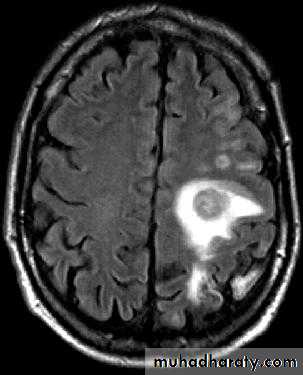

Brain Abscess MRI